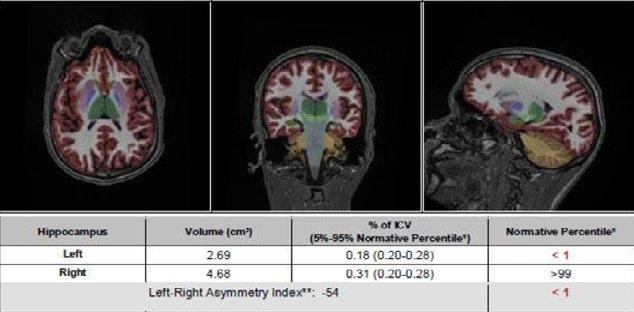

Fig 1: Next generation MRI is being used to gather data on brain tissue volumes

From this season at Manchester United Football Club, we have started to gather data by using MRI (see fig 1) to measure volumes of brain tissue in specific areas, to monitor for a decrease in volumes over time. If the volumes become unusual or deviate from the norms that we would expect, it may help us identify early changes of CTE that need closer monitoring. This is a new, long-term data gathering study in our cohort of players that has been facilitated with the new next generation MRI3 now in place at our medical centre.